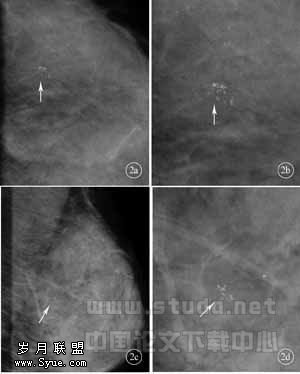

影像学检查是早期发现乳腺癌的关键,乳腺X线摄影是迄今公认的乳腺疾病的首选检查方法,尤其对表现为单纯微钙化的导管内癌的诊断具有重要意义。但由于X线检查对近胸壁处的肿块易遗漏、致密型乳腺肿块的对比度差、乳腺X线摄影设备在基层医院普及率不高等诸多因素的影响,致使其应用受到一定的限制。而超声成像由于无放射线辐射、无需压迫、使用方便、价格低廉等深受临床医生和患者的喜爱。因此,如何合理应用现有的检查手段,采取最简捷、有效、无创、经济的途径获得明确诊断,成为乳腺影像工作者长期探索的问题之一。目前,在欧美发达国家,乳腺X线检查和超声成像已经成为乳腺影像学检查的黄金组合。国内亦有部分学者开始探讨利用超声成像提高乳腺X线检查的敏感性和特异性[4~8]。但有关乳腺X线检查、超声成像以及二者联合应用对乳腺微小病变的诊断价值尚未见报道。为了比较乳腺X线检查、超声成像以及二者联合应用对乳腺微小病变的诊断价值,本研究参考美国放射学会制定的乳腺影像报告和数据系统(BI-RADS)[3]的分级方法,根据乳腺X线表现、超声成像、二者联合将乳腺病变分为四级,并以病理学诊断为金标准,比较三种方法对乳腺病变和微小乳腺病变的诊断能力。研究结果显示,对于微小乳腺病变,超声成像的敏感性低于X线检查,但无统计学差异。超声漏诊的4例病变在X线片上均表现为单纯簇状微钙化(图2),结合X线检查后复诊才发现病变。说明乳腺X线摄影的优势在于对表现为单纯微钙化的导管内癌的敏感性高于超声成像,适宜于乳腺癌的常规筛查。但乳腺超声成像在乳腺癌的检出和诊断中亦具有重要价值,尤其是近年来乳腺癌的发病有年轻化的趋势,此年龄段乳腺腺体丰富致密,加之我国妇女的乳房偏小,脂肪少、缺乏对比,乳腺X线摄影敏感性较差,具有一定局限性。此时乳腺超声成像的价值更为突出。但超声扫描必须结合X线检查才能保证质量。本组联合诊断对微小乳腺病变诊断分级的各项指标均优于单纯采用乳腺X线检查和超声成像,X线检查所漏诊的1例病变在超声成像中表现为低回声并有较丰富的血流,两者联合得以正确诊断。

图2 患者,女,35岁,左乳外后方中纯微钙化, 位置较深,超声漏诊,结合x线复诊,发现病变,行超声引导下定位,病灶完整切除,术后病理:乳腺导管内癌;a:左乳轴位;b:轴位局部放大;c:左乳斜位;山斜位局部放大)